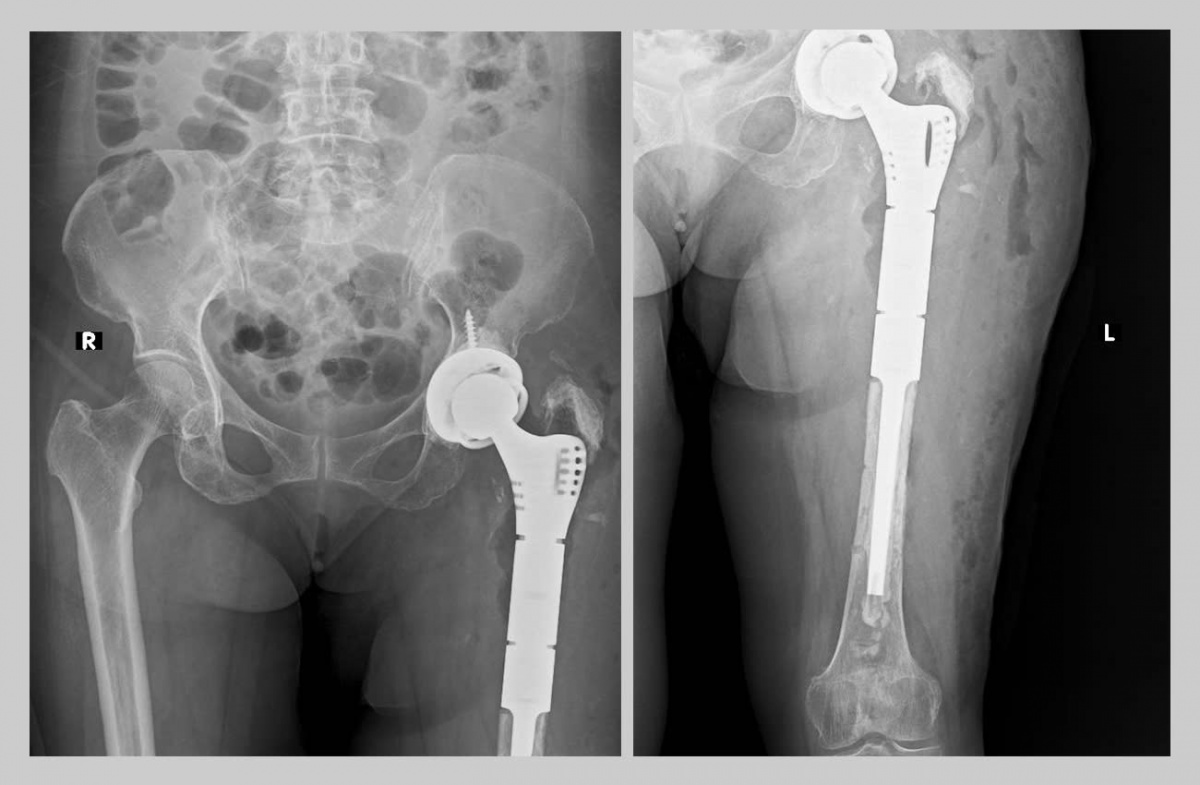

Bệnh viện Trung ương Huế vừa thực hiện thành công ca phẫu thuật thay khớp háng và xương đùi bằng Megaprosthesis. Kỹ thuật này được xem là giải pháp tối ưu cho những trường hợp tổn thương nặng mà trước đây có nguy cơ cao phải cắt cụt chi.

Bệnh viện Trung ương Huế cho biết, vào ngày 24/6, đơn vị vừa thực hiện thành công ca phẫu thuật thay khớp háng và xương đùi bằng Megaprosthesis. Đây là một kỹ thuật chuyên sâu bảo tồn chi thể cho người bệnh trong lĩnh vực phẫu thuật chấn thương chỉnh hình.

Bệnh nhân là bà P.T.X. (71 tuổi) trú tại phường An Cựu, TP. Huế, có tiền sử thay khớp háng nhân tạo cách đây 17 năm và từng phẫu thuật lại do lỏng khớp một năm trước. Hơn 4 tháng gần đây, bệnh nhân xuất hiện đau tăng khi đi lại, phải sử dụng gậy hỗ trợ, vận động khó khăn và suy giảm chất lượng sống.

Qua thăm khám và chẩn đoán hình ảnh, các bác sĩ ghi nhận tình trạng tiêu xương lan rộng, gãy quanh khớp háng nhân tạo, gãy phương tiện kết hợp xương, lệch trục và rút ngắn chi trên 7cm. Đây là một tổn thương nặng nề và phức tạp, có nguy cơ mất chức năng chi thể nếu không không can thiệp kịp thời.

Sau khi được nhập viện tại Khoa Phẫu thuật Khớp – Y học Thể thao thuộc Trung tâm Chấn thương chỉnh hình – Phẫu thuật tạo hình, Bệnh viện Trung ương Huế, bệnh nhân được chỉ định phẫu thuật thay lại khớp háng và hơn một nửa xương đùi bằng Megaprosthesis.

Sau gần 4 giờ đồng hồ với sự hỗ trợ tối đa về nhân lực và trang thiết bị hiện đại, ca mổ do TS.BS. Nguyễn Nguyễn Thái Bảo, Trưởng Khoa Phẫu thuật Khớp – Y học Thể thao cùng ê-kíp thực hiện đã diễn ra thành công, khôi phục cấu trúc và chức năng chi thể, đồng thời phục hồi chiều dài hai chân bằng nhau.

Sau phẫu thuật, bệnh nhân phục hồi tốt, có thể tự đứng và bắt đầu quá trình tập phục hồi chức năng.

Các bác sĩ ở Huế tái tạo khớp háng và hơn nửa xương đùi cho bệnh nhân. Ảnh: ĐVCC.